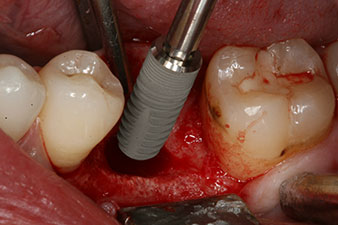

The implant was placed as planned after thorough removal of the granulation tissue (blueSky, bredent).

The torque used for the machine-driven placement was 43 Ncm. In addition, after screwing a measuring post (SmartPeg) specially matched to the implant, the ISQ value was measured with the probe of the W&H Osstell ISQ module.

This module is an optional extra for the W&H Implantmed and is docked to the implantology motor (see Fig. 11). The dimensionless ISQ value immediately after insertion was 64 orovestibular and 68 mesiodistal (maximum value = 100).